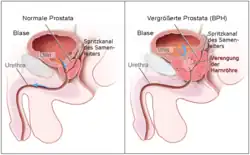

The alpha blockers mostly act in our smooth muscles, especially the ones that control the size of vessels.[3] Thus, alpha1 blockers can dilate blood vessels and decrease the blood pressure.[3] Depending on its site of action, it can be used to treat different diseases.[3] They can be used to treat signs and symptoms of benign prostatic hyperplasia, hypertension (but not as first line agent), pheochromocytoma, extravasation management and reversal of local anesthesia.[3]

There are some off- label use as well, such as chronic prostatitis and lower urinary tract symptoms in males, ureteral calculus expulsion, ureteral stent-related urinary symptoms.[3] It can be used in post-traumatic stress disorder, Raynaud phenomenon, hypertensive crisis, extravasation of sympathomimetic vasopressors, problem with urine related to neurogenic bladder, functional outlet obstruction and partial prostate obstruction.[3]

As alpha 1 blocker will dilate blood vessels, it lowers the blood pressure.[3] Thus, it contraindicate to patients with a history of orthostatic hypotension and in current use of phosphodiesterase inhibitors.[3] Moreover, alpha 1 blocker should not be given to patients with heart failure since it expands blood volume.[13]

In 1978, a successful alpha blocker, phenoxybenzamine was confirmed to be clinically beneficial through a randomized, placebo-controlled study.[22] It was the first alpha blocker which was used for treating Benign Prostatic Hyperplasia.[22]

Another Alpha Blocker Prazosin, which was the first drug selective to alpha 1 receptor, was developed in 1987[22] for the therapy of Benign Prostatic Hyperplasia. Other alpha blockers are then introduced for several diseases.[22]